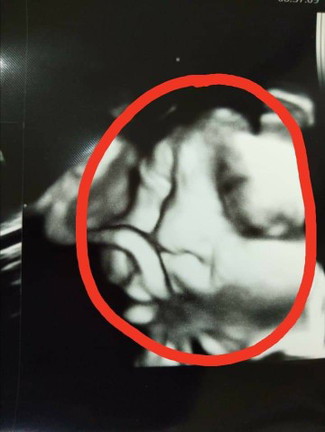

ดูทำหน้าสิ

โกธรอะไรเเม่น่าาา?

ยังดีที่ให้เห็นหน้าค่ะ บ้านนี้ว่ายหนี มือปิดบ้างค่ะ

เอ็นดูน้องค่ะ😅😅